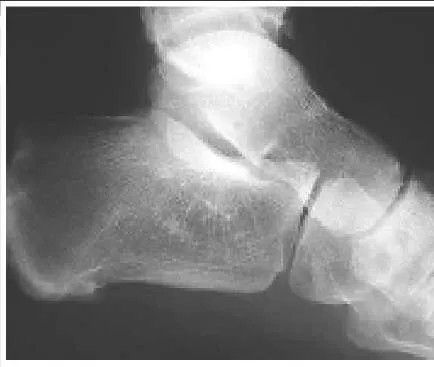

A 14-year-old boy presents for treatment of a painful foot, which has been present for 2 years. He has limited his athletic activities. He has similar symptoms in the opposite foot, although not as severe. On clinical examination, the alignment and appearance of the foot are normal; motion of the foot and ankle is good; and some discomfort is present in the sinus tarsi. Standard radiographs, of which the lateral view is presented, include anteroposterior, lateral, and oblique views. Because the diagnosis is unclear, more imaging studies are required. The next study to obtain is:

Correct Answer: Axial views of the subtalar joint (Harris)

The radiograph demonstrates changes in the subtalar joint suggestive of a middle facet coalition. Note the sclerosis of the joint surface. Although a computed axial tomography scan may be helpful, standard axial views of the subtalar joint (Harris) taken in the plane of the joint are usually diagnostic of tarsal coalition. Motion of the subtalar joint may be normal in the adolescent with a tarsal coalition.